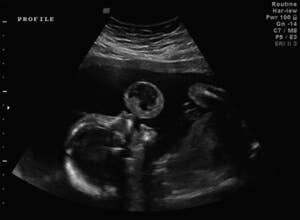

It was an expectant parents’ worst nightmare: an ultrasound image revealed that their unborn baby had a large tumor growing from its mouth. Even worse, if the tumor were allowed to grow for the duration of the pregnancy, there was a good chance the baby would die from excessive bleeding. The only way to save the baby’s life would be to perform a difficult and risky operation to remove the tumor while the baby was still in the womb. The operation, perhaps the first of its kind, was performed in 2010. The now 20-month-old Leyna Mykaella Gonzalez is doing fine, and the surgeons who saved her life are ready to tell her amazing story.

Back in early 2010 Tammy Gonzalez, then 20 weeks pregnant, saw what resembled her baby blowing a bubble about the size of a peach on an ultrasound image. Doctors determined the “bubble” to be a fetal oral teratoma, a rare tumor that occurs in between one in 35,000 to 200,000 live births. Tammy and her husband were told that the baby stood little chance of surviving birth, and even if she did, she would have to undergo an immediate tracheotomy to allow her to breathe, and numerous subsequent surgeries. Furthermore, the baby would probably be disfigured.